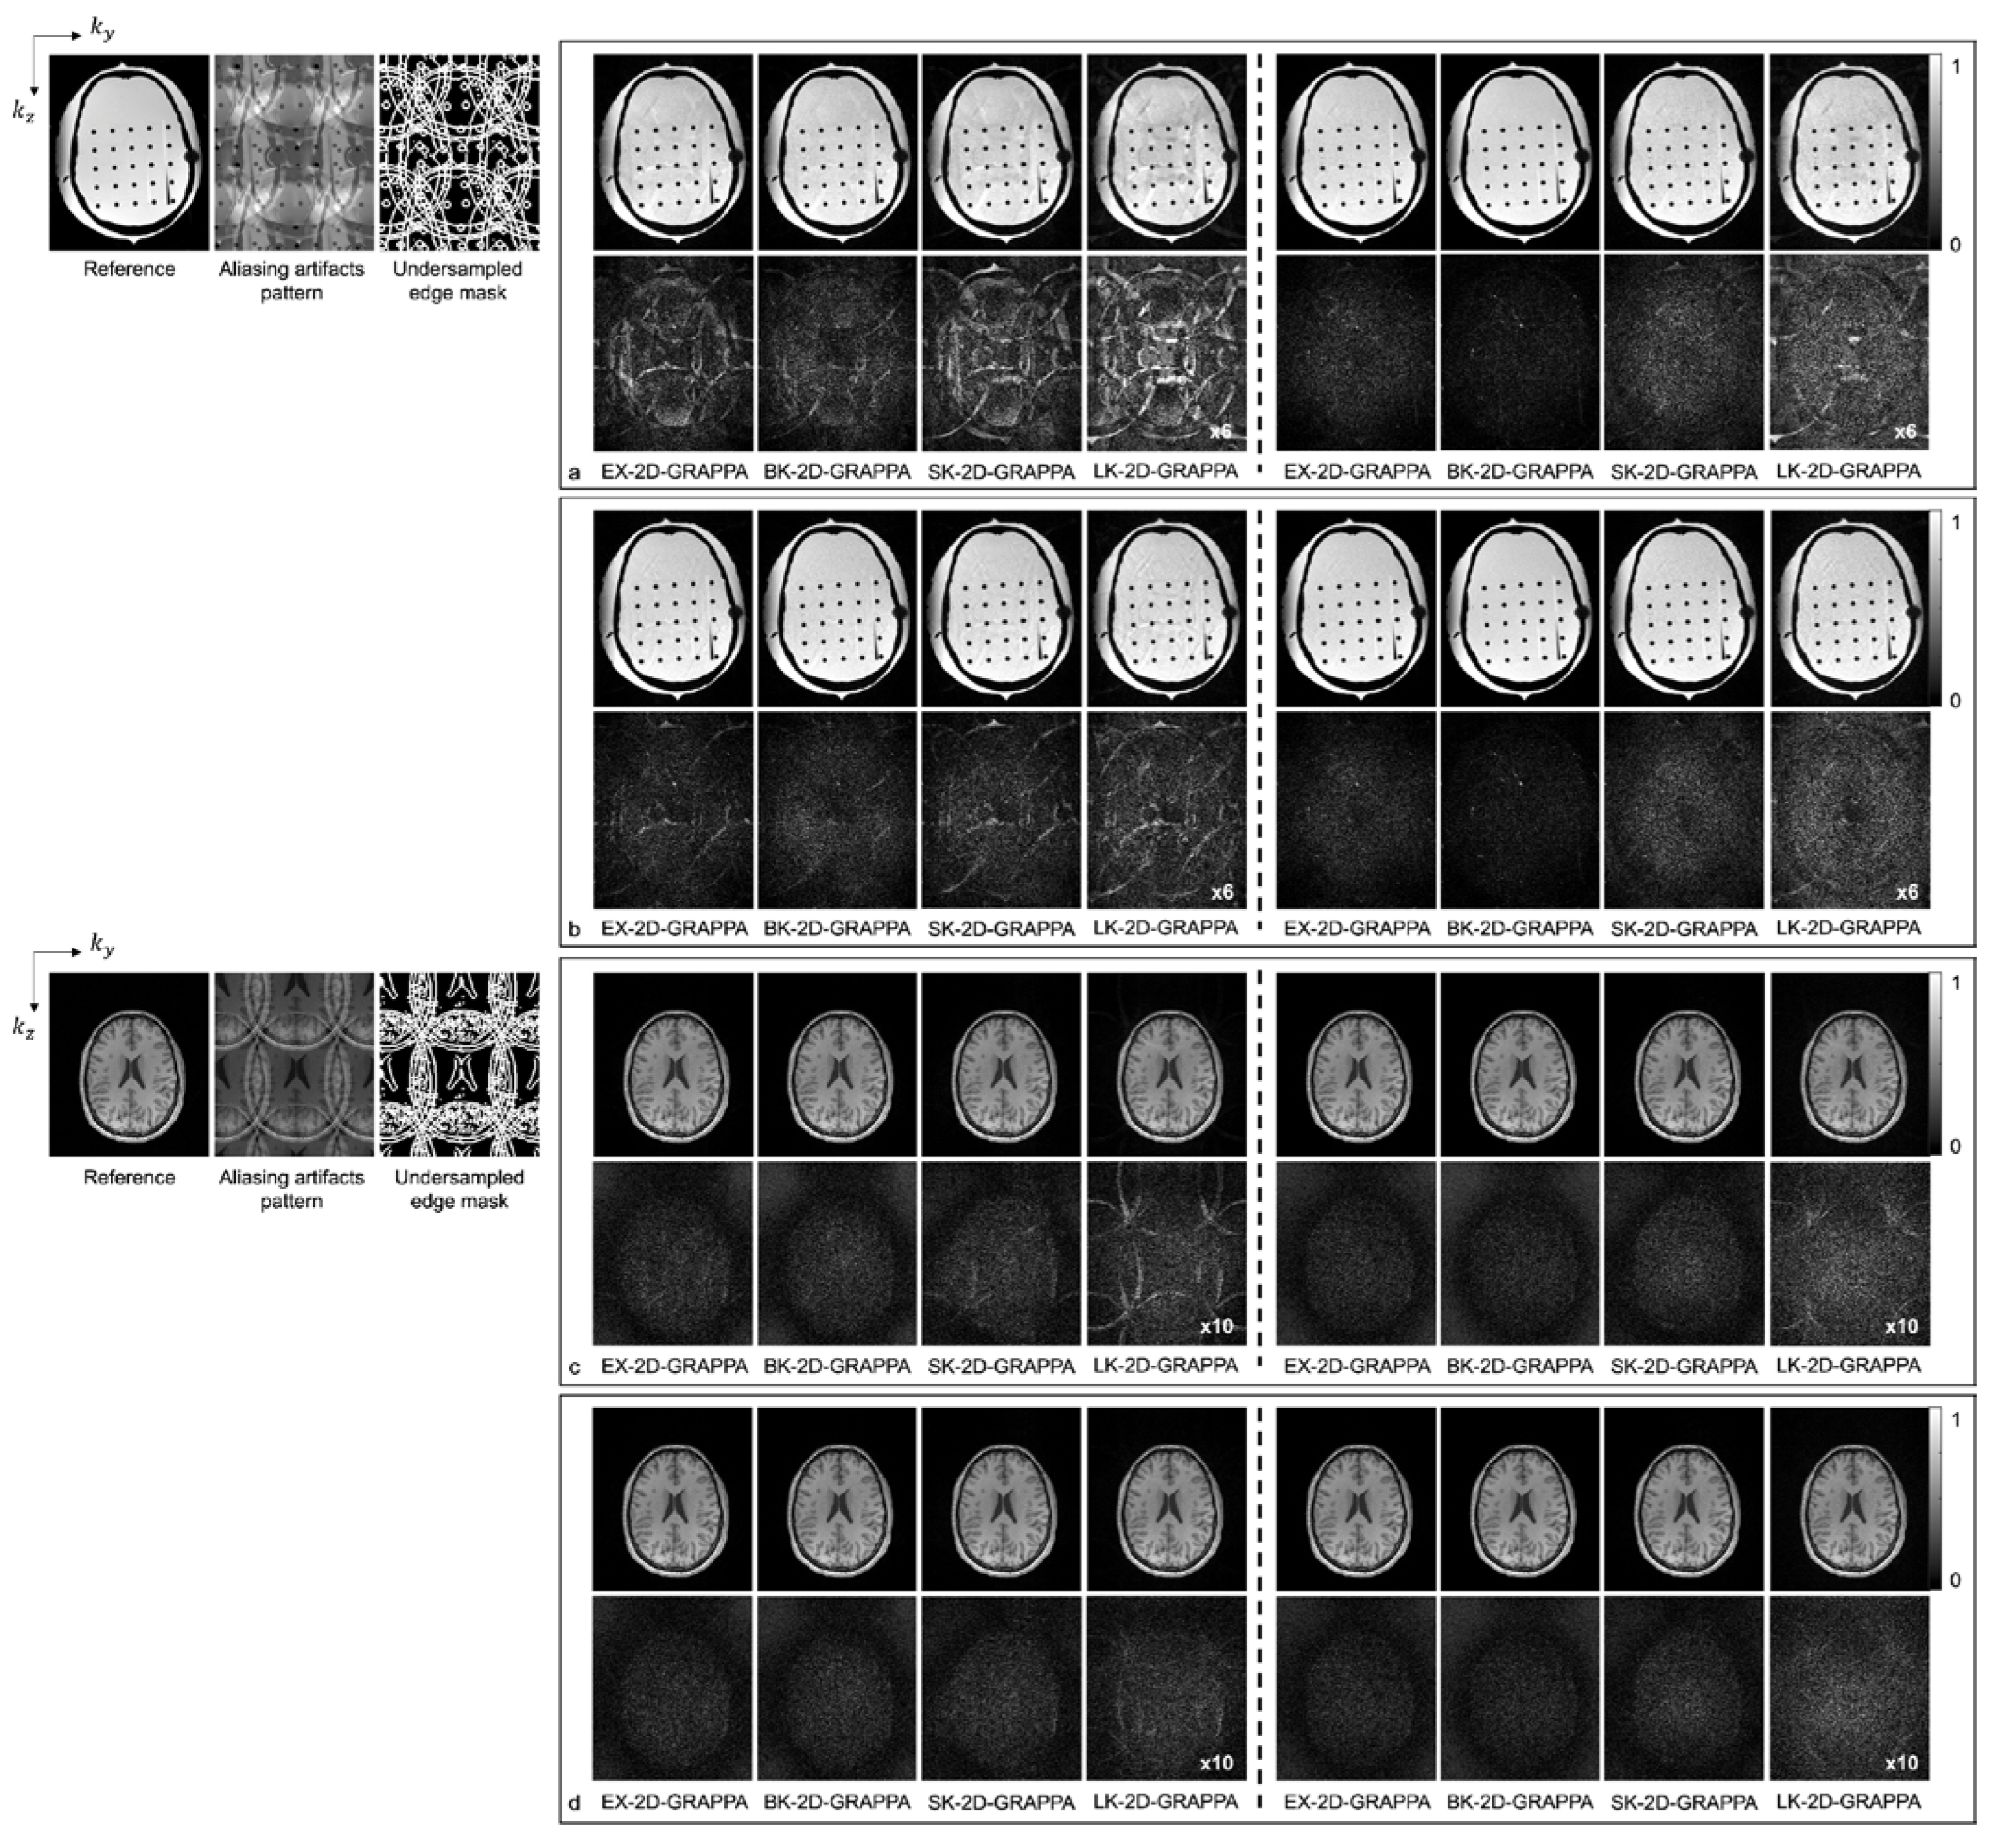

4. Results